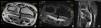

A 62 year-old male, by profession a butcher. He had a history of gout which was poorly controlled by sporadic treatment. He presented at the rheumatology department with “tingling” in the fingers of both hands which was more acute in the left hand (right-handed patient) and a loss of fine motor skills. An electroneurogram was performed with showed severe compression of the sensitive fibers of the bilateral median nerve, more acute in the left. Due to suspicion of a tophus being the cause of the CTS, NMR was performed. Findings (Fig. 1) were as follows: tophus inside the sheath of the flexor tendons at carpal level. The patient underwent surgery and the surgeon confirmed the existence of the tophus. The patient is currently receiving hypouricaemic therapy and there are no clinical signs of left CTS.

ConclusionCTS caused by gouty tophus is extremely rare. Its determination by NMR is diagnostic. In selected cases where there is high clinical suspicion, atypical CTS symptomatology, in patients with poorly controlled gout, it may be a supplementary test requested as diagnostic support and for the planning of treatment.